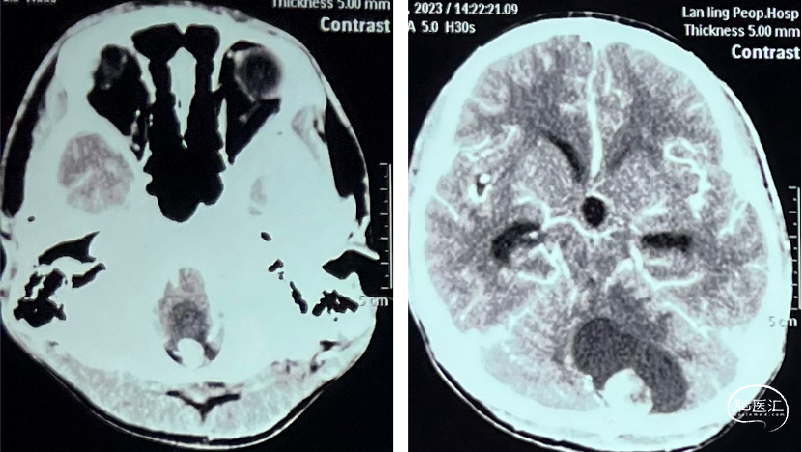

术前检查

术前CT

image.png